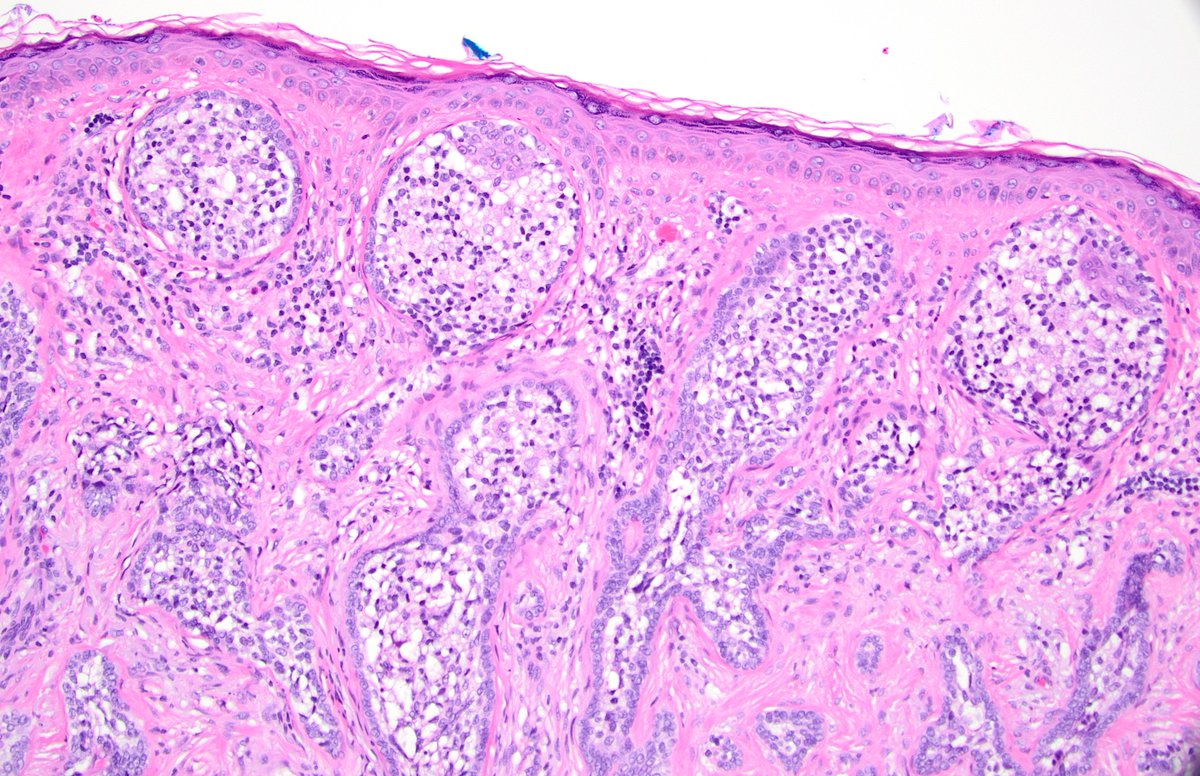

@dgbrackett

One of those "it's very distinctive and it has a name but I don't know what it is" cases Could it be a cutaneous lymphadenoma? (AKA adamantinoid trichoblastoma) I've never made the Dx before #dermpath